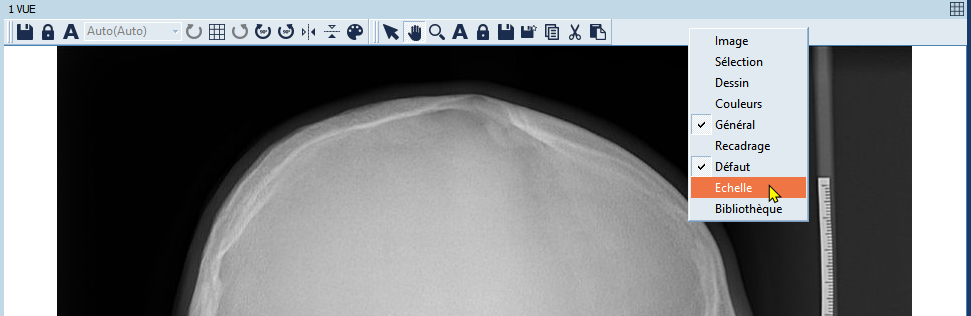

- Mettez le menu "Échelle" dans le visualiseur.